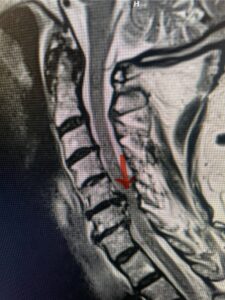

Another patient, a 77 year-old female, presents with pain, numbness, and weakness of her arms and difficulty with balance over a 6-month period. MRI revealed severe osteophytic disease at C5-C7 with cord compression (Fig. 4). Further work-up by fine-cut cervical CT to evaluate the nature of compression revealed a completely calcified osteophyte (Fig. 5). Although the patient had a good lordosis and a posterior cervical approach would accomplish an adequate decompression, we elected to perform a two-level anterior cervical discectomy and fusion. This particular osteophyte is formidable because of its size but the compression was all anterior and would be a less invasive approach. Fortunately, during the procedure, the patient had a fair amount of osteoporosis which allowed the osteophyte to be drilled and bit away with considerable ease. Interestingly, the C6 7 osteophyte which was more a sheet of osteophyte was more challenging to remove. In the end the decompression went well, and we placed two interbody devices filled with bone graft with plates at each level (Fig. 6). The patient had a nice recovery with immediate reduction of pain and numbness. This case demonstrates the importance of recognition of cervical myelopathy in its early stages. A significant reversal of function is generally the rule if the patient has appropriate correlative findings on exam and MRI, particularly with long tract distribution weakness development within a year time period.

Figs 4a: Sagittal and axial T2-weighted cervical MRIs demonstrating large osteophyte worse at C5-6 compressing spinal cord more eccentrically to the left (red arrows)

Fig 5a: Sagittal and axial cervical fine-cut CT scan demonstrating severe osteophyte formation causing cord compression at C 56 (red arrow)